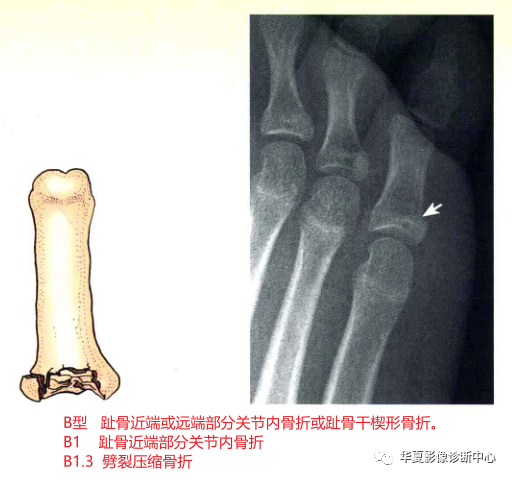

B型:趾骨近端或远端部分关节内骨折或趾骨干楔形骨折。

B1:趾骨近端部分关节内骨折。又分为:

B1.1:撕脱或劈裂骨折;

B1.2:压缩骨折;

B1.3:劈裂压缩骨折。